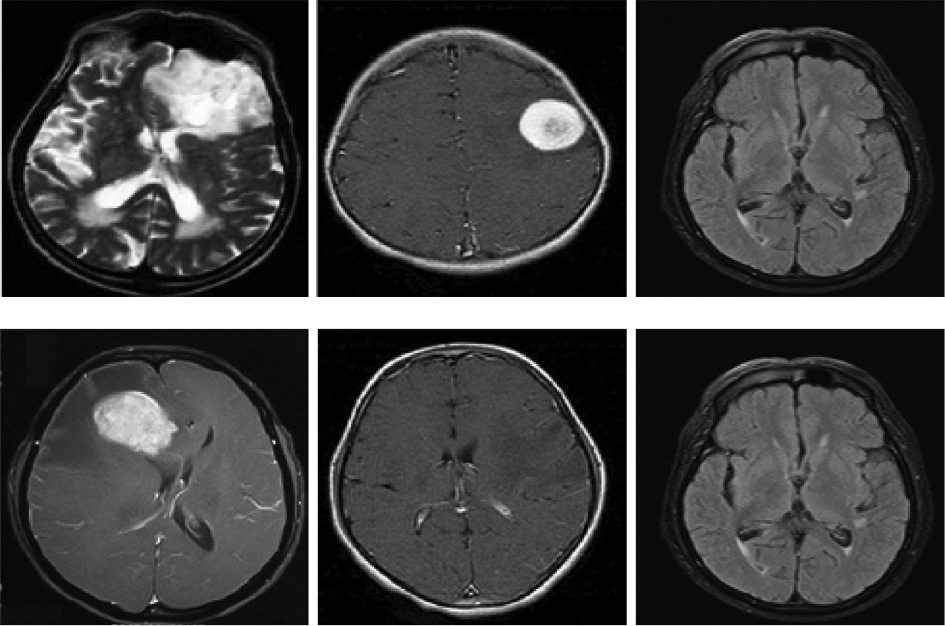

The MRI brain image data set is effectively employed in the innovative image segmentation and classification techniques, which are obtained from the publicly accessible sources. The corresponding image data set contains 20 brain MRI images of which 15 brain images are with tumor and the remaining five brain images are without tumor. The brain image data set is subdivided into two distinct sets such as the training data set and the testing data set. The training data set is effectively utilized to segment the brain tumor images, and the testing data set is employed to evaluate the performance of the novel approach. Here, 10 images are elegantly employed for the training purpose, and the residual 10 images are effectively used for the testing purpose. Figure 4 illustrates certain sample MRI images with tumor and without tumor.

Figure 4: Sample Experimental Used Images.

Figure 4:

Sample Experimental Used Images.